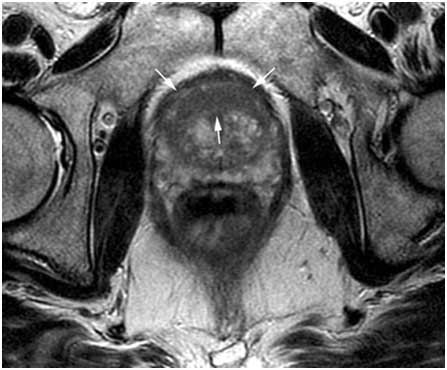

MRI-guided trans-rectal prostate biopsy

Images from the MRI scanner allow the surgeon to track the needle and to guide the tip into a target in the prostate. By using our Prostate Biopsy Robot, the surgeon controls the robot “remotely”, thus improving safety and accuracy. The robot can extract cells from the prostate within 2mm.